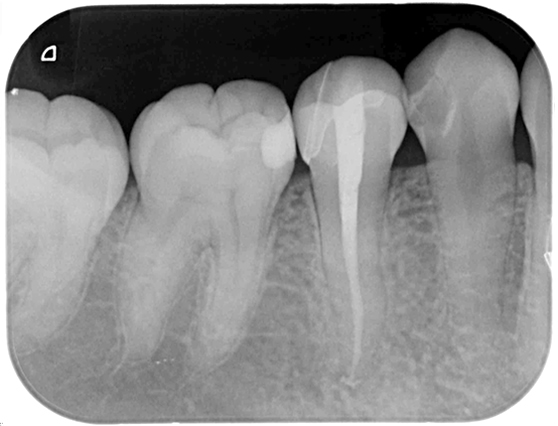

根管治療 症例9

| 治療前 | ![]() |